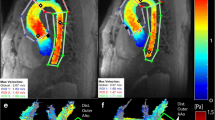

Characteristics of the CoA patients and subgroups are shown in Table 1. Non-significant correlations within the entire patient population (n = 21) were found between the following parameters: the age at correction and MRI, PWV in the proximal and descending aorta, PWV ratio, and peak WSS in the ascending aorta, aortic arch, and descending aorta. And, for the same parameters, non-significant group differences between the BAV and TAV subgroups were found (respectively, n = 12 and n = 9). For patients with a TAV, a significant good correlation was found between age at correction and descending aorta PWV (rs = 0.80, p = 0.010, Fig. 2), indicating higher values of descending aorta PWV for patients with a TAV that underwent correction of CoA at an older age. Such a correlation was absent for patients with BAV. Between the subgroups without reobstruction and with reobstruction (respectively, n = 12 and n = 9), significant differences were found for the peak WSS in the aortic arch (3.9 ± 1.3 Pa versus 6.5 ± 2.2 Pa, respectively; p = 0.003) and descending aorta (5.0 ± 1.3 Pa versus 6.7 ± 1.1 Pa, respectively; p = 0.005), indicating higher peak WSS values for patients with a reobstruction proximally and distally to the lesion. The statistical analysis within subgroups subdivided on both the aortic valve morphology and the presence of reobstruction was not performed, due to small population sizes within these subgroups. Examples of three-dimensional magnitude WSS maps of patients, subdivided on the aortic valve morphology and the presence of reobstruction, are shown in Fig. 3. The examples demonstrate higher peak WSS in the aortic arch and descending aorta for patients with reobstruction compared to those without reobstruction.

Three-dimensional magnitude wall shear stress maps of patients with aortic coarctation subdivided on both the aortic valve morphology and the presence of reobstruction, incorporating the anatomical segments: Asc AO, ascending aorta; Arch, aortic arch; Desc AO, descending aorta. a Example of patient with tricuspid aortic valve without reobstruction. b Example of patient with tricuspid aortic valve with reobstruction. c Example of patient with bicuspid aortic valve without reobstruction. d Example of patient with bicuspid aortic valve with reobstruction

The observed peak WSS differences in the aortic arch and descending aorta between the patients without and with reobstruction imply that local luminal narrowing results in an increased haemodynamic load on the aortic wall proximally and distally to the lesion. This effect was predominant within the aortic arch. Multiple studies indicated that endothelium lining properties are highly sensitive to the applied WSS on the vessel wall, which promotes adaptive dilation or structural remodelling of the artery wall during high WSS [11]. Therefore, different disease progression could potentially be expected for patient with and without postoperative obstructions. This endorses the initial curative reconstruction and longitudinal follow-up examination of corrected CoA patients. However, the surgical reconstruction is associated with the formation of abnormal postoperative aortic haemodynamic due to aorta compliance [8] and geometry [26, 27] modifications. For example, it has been demonstrated that the postoperative aortic arch geometry in CoA patients affects the PWV [27] and peak WSS magnitude and location [26]. Additionally, the presence of an aortic reobstruction was defined as a maximal flow velocity larger than 2.5 m/s. This criterion is arbitrary since peak flow velocity alone does not always discriminate patients without obstruction and those with obstruction [22]. Therefore, a single Doppler echocardiogram measurement will probably not be the decisive factor for reintervention in most clinical centres.